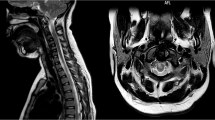

Magnetic resonance imaging (MRI) on admission demonstrated diffuse spinal cord edema with increased signal on T-2 weighted images and faint enhancement with gadolinium infusion. Urologic symptoms improved with steroids but motor function was never fully regained. Repeat MRI of the spinal cord several months later showed diminution of cord diameter with resolution of edema and signal abnormality.

Based on the clinical course and MRI findings, the daignosis of acute transverse myelitis was made. The association of previously received DPT immunization and the genesis of transverse myelitis is explored.